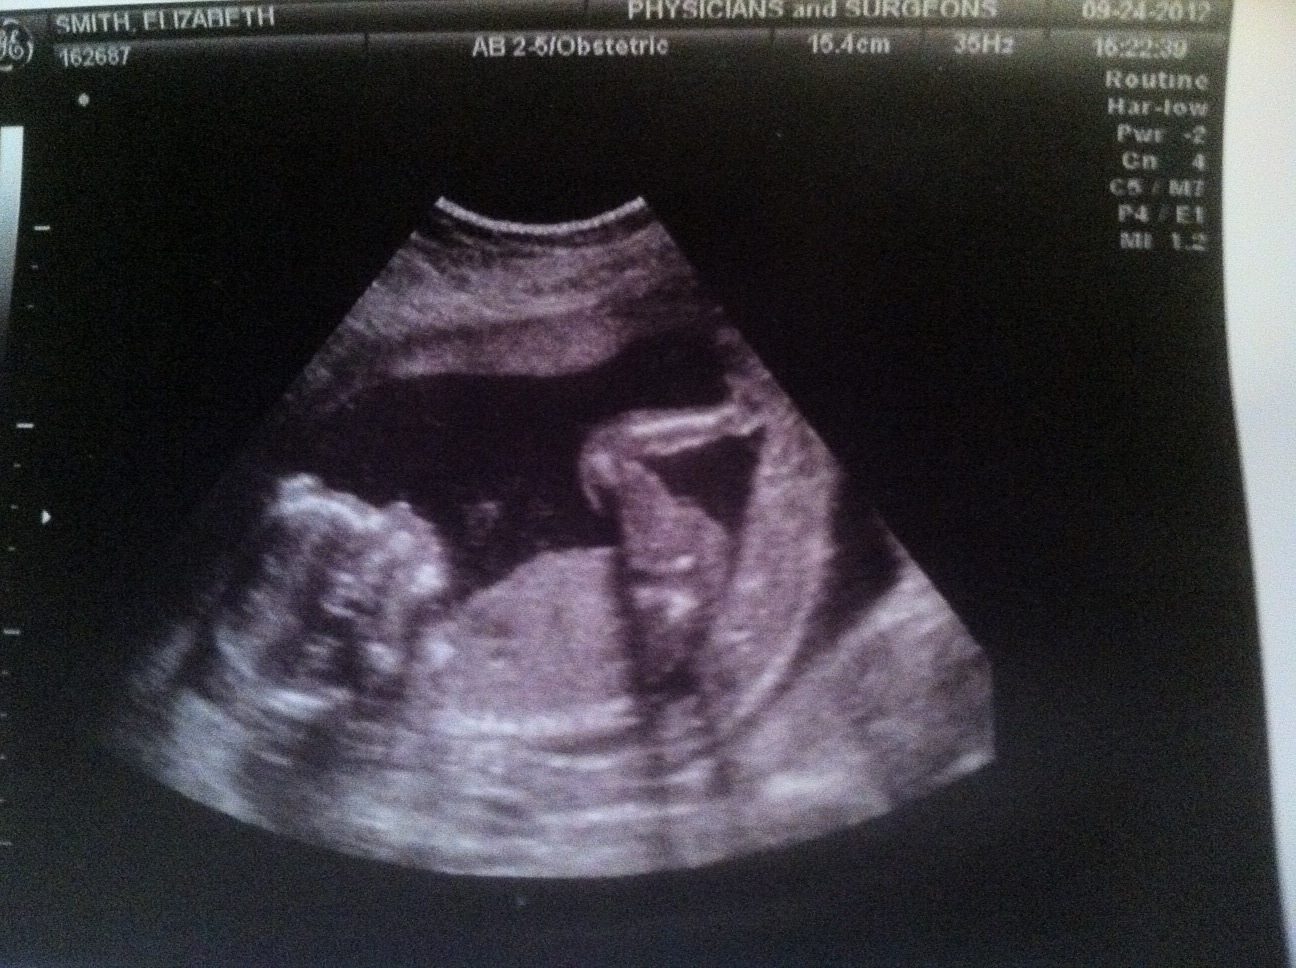

Out Of The Blue: 17 Week Update And Anatomy Ultrasound

Out of the Blue: 17 Week Update and Anatomy Ultrasound outofthebluetoo.blogspot.com

ultrasound week weeks anatomy update profile handsome man